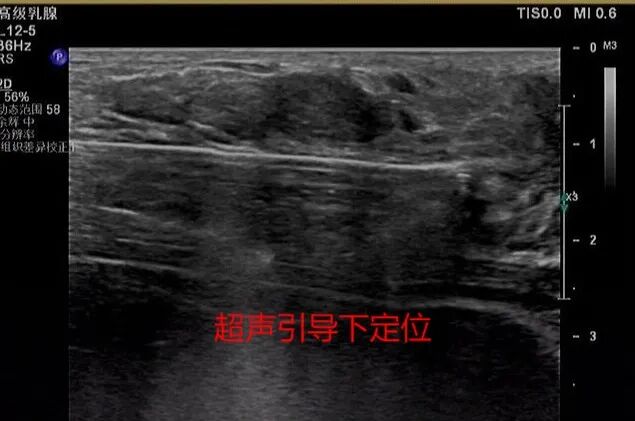

麦默通旋切术是在超声定位引导下,通过计算机控制的真空辅助高速旋切乳房治疗性诊断性微创手术,它可以准确的一次切除多个乳房肿块及对肿块进行病理活检,及时发现乳腺癌。

2月18日,泰州四院超声科专家汤四新、李娅成功为王女士进行手术,解决了她的“心头之忧”,既切除了乳腺结节,又保住了乳房的美观。手术采用局部麻醉,在B超系统的引导下,由旋切探针从乳房肿块上3-4mm处插入待检区域,进行轻柔的真空抽吸和切割,完成肿块的切除,为检查和评估取出组织。手术仅有2mm长切口,不用缝针,单用普通胶贴贴合即可。